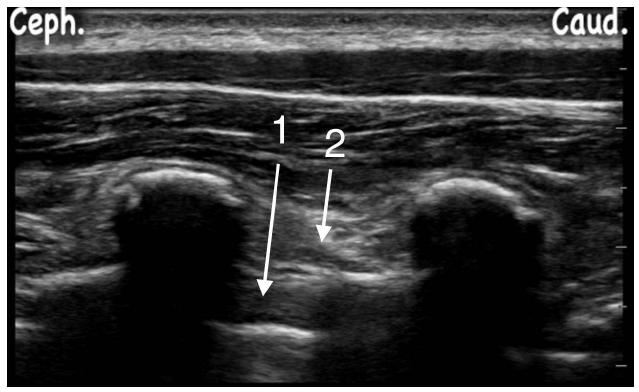

Observe a figura a seguir e assinale a alternativa CORRETA: